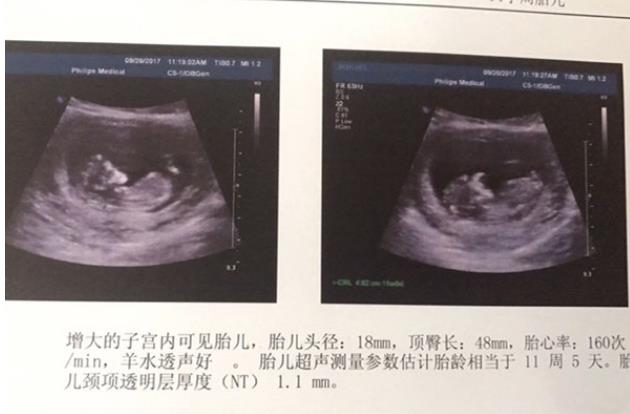

看到這張報告,我和老公超高興!終于寶寶安營扎寨了。我所付出的都值得了。大慈大悲的觀音菩薩一直保佑著我們!期待十天后的彩超,寶寶更棒!